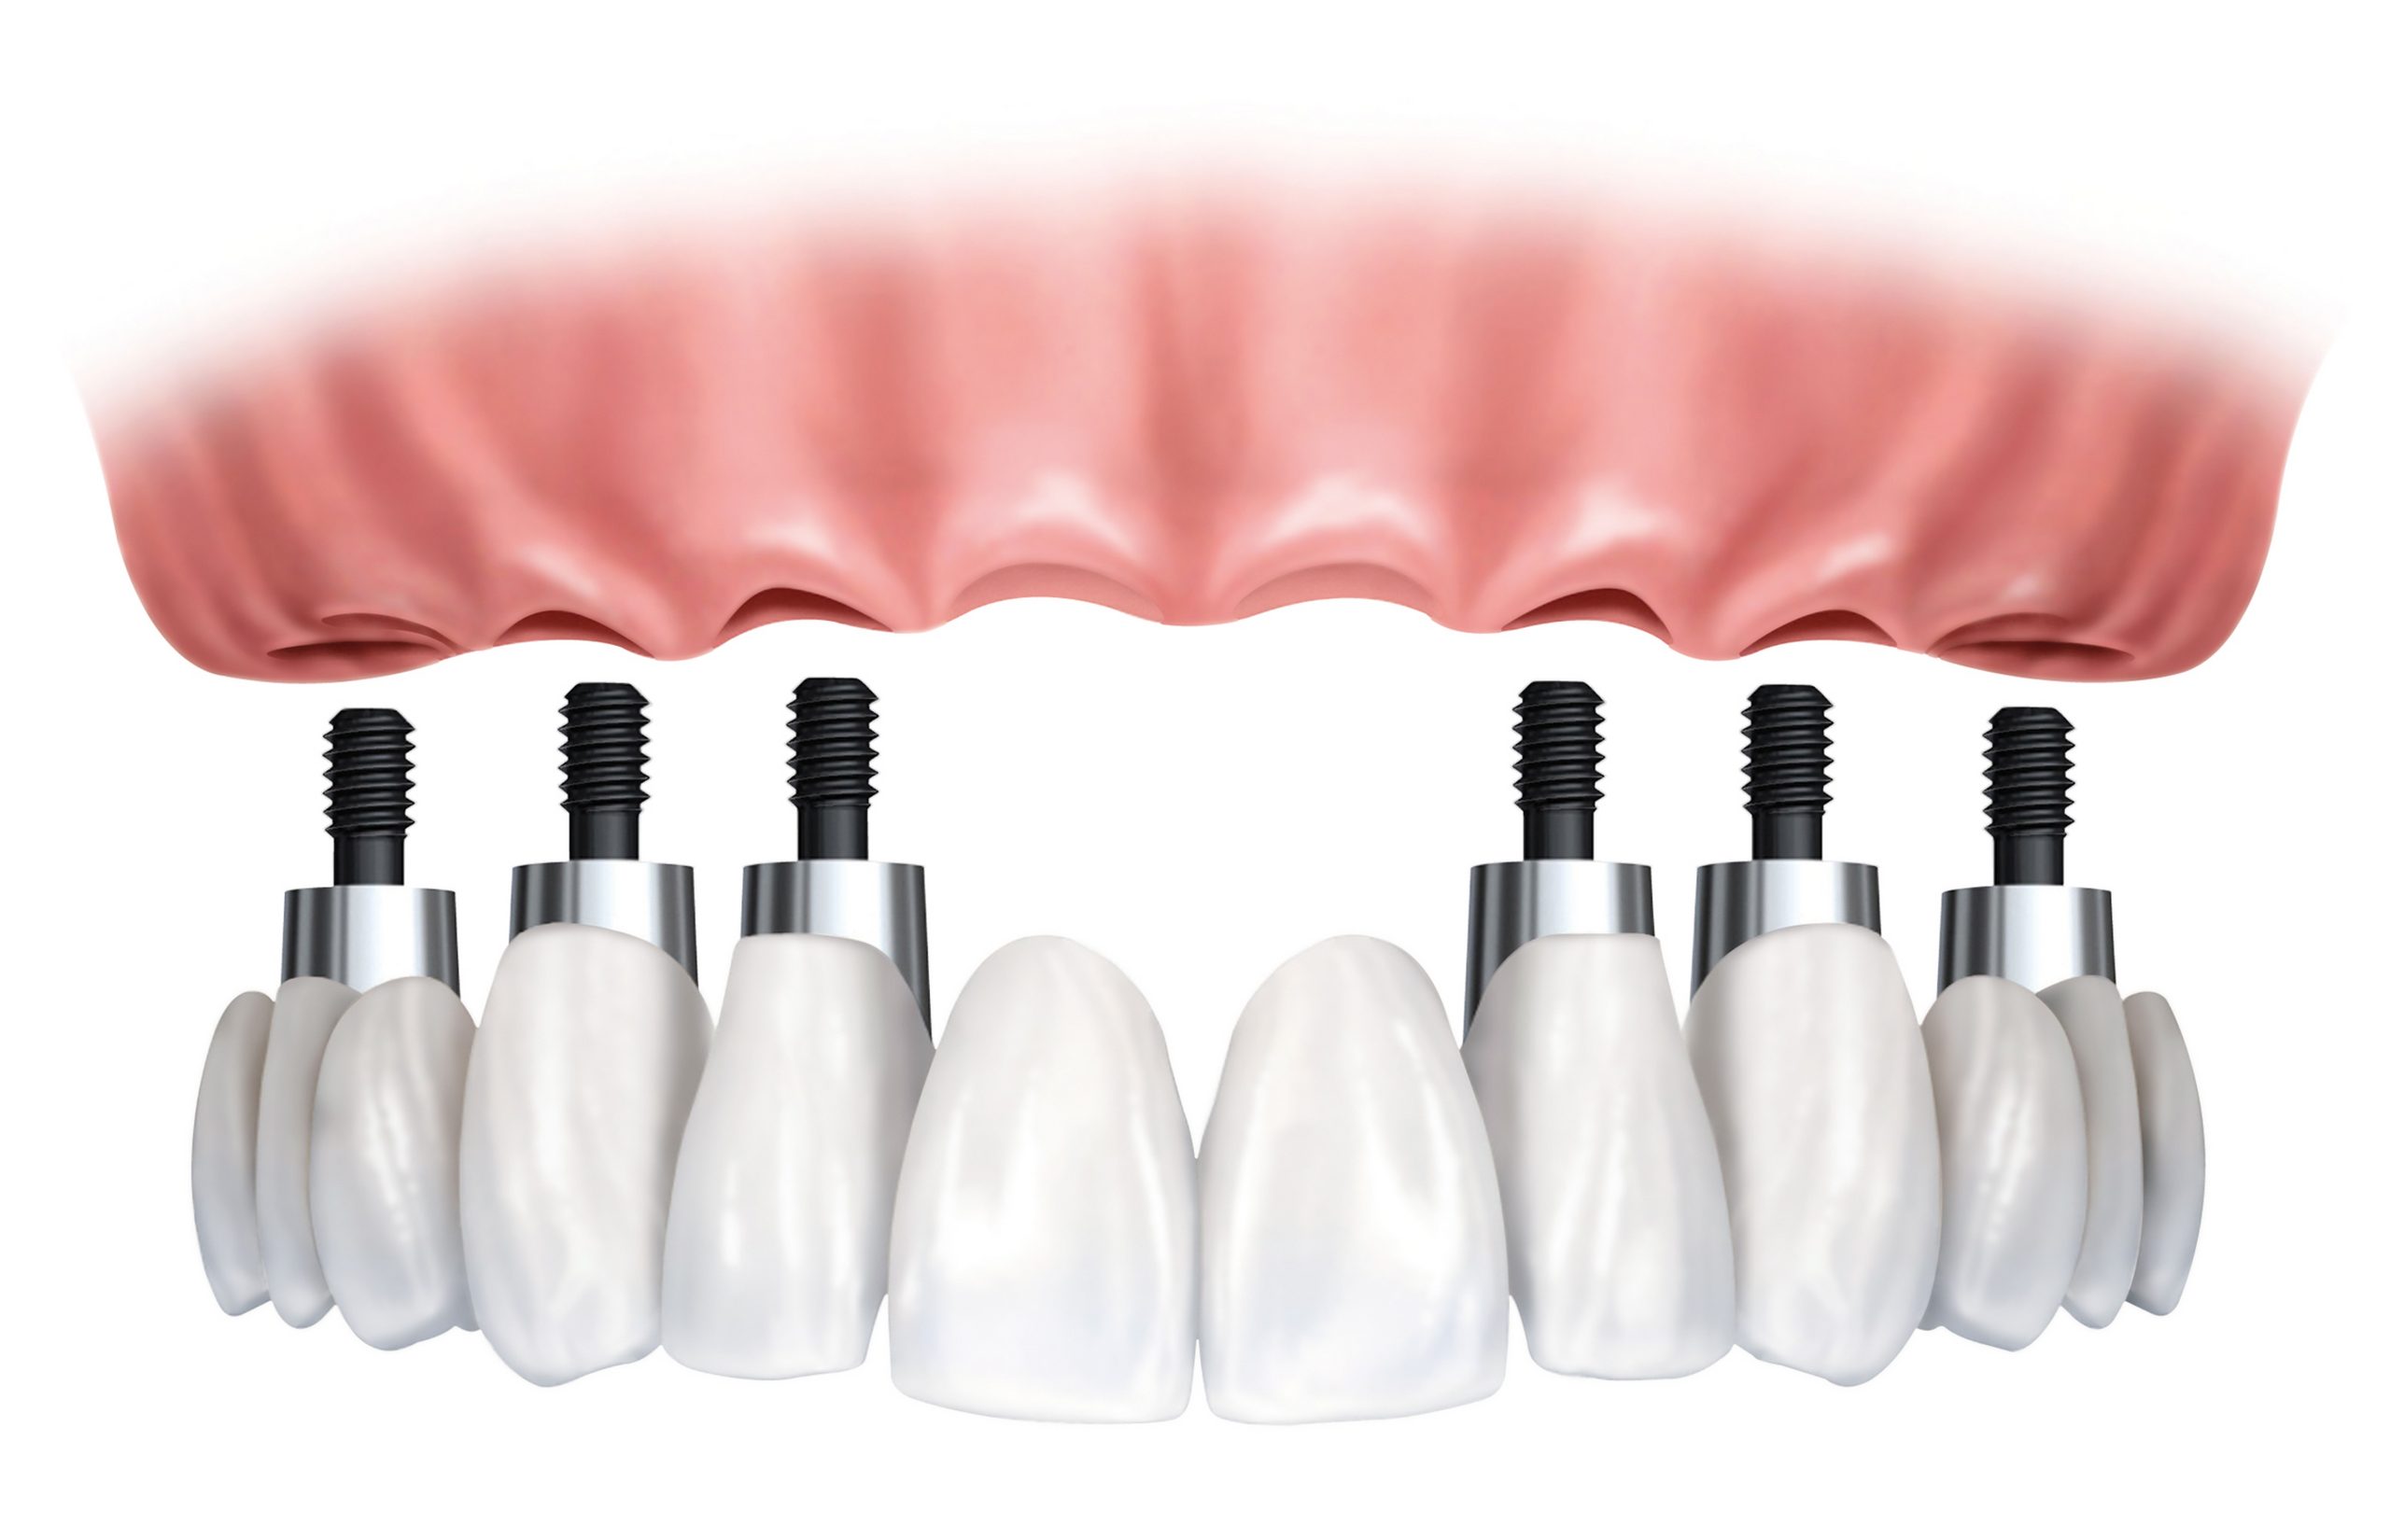

Τα οδοντικά εμφυτεύματα αντικαθιστούν τις ρίζες των δοντιών παρέχοντας ένα ισχυρό θεμέλιο για τη σταθερή ή κινητή αποκατάσταση των απολεσθέντων δοντιών, εφάμιλλων των φυσικών.

Τα οδοντικά εμφυτεύματα προσομοιάζουν τόσο στην εμφάνιση όσο και στην αίσθηση τα φυσικά δόντια.